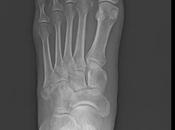

Desgarro muscular de la cabeza larga del bíceps femoral

Motivo de estudio: Revisión por antecedente de desgarre, dolor femoral (datos proporcionados por paciente).Técnica: En resonador de 1. Leer el resto